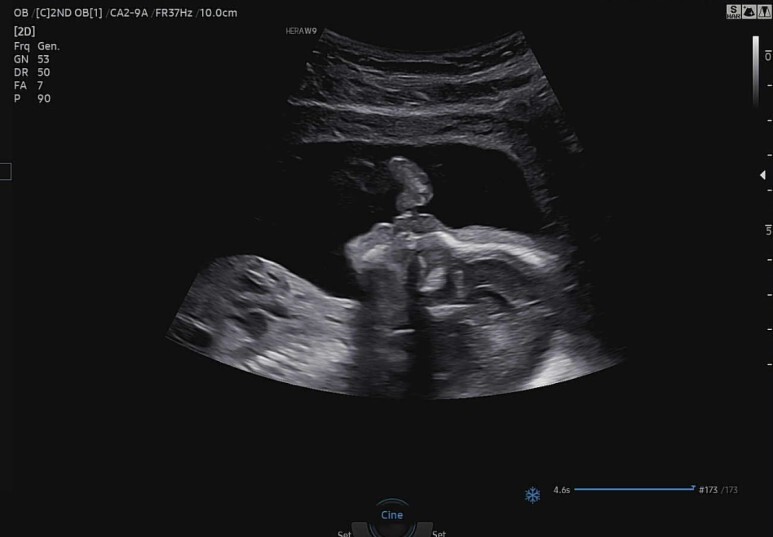

꿀잠이 이마와 코뼈 확인

콧구멍이랑 인중도 확인하고 정밀 초음파 종료.